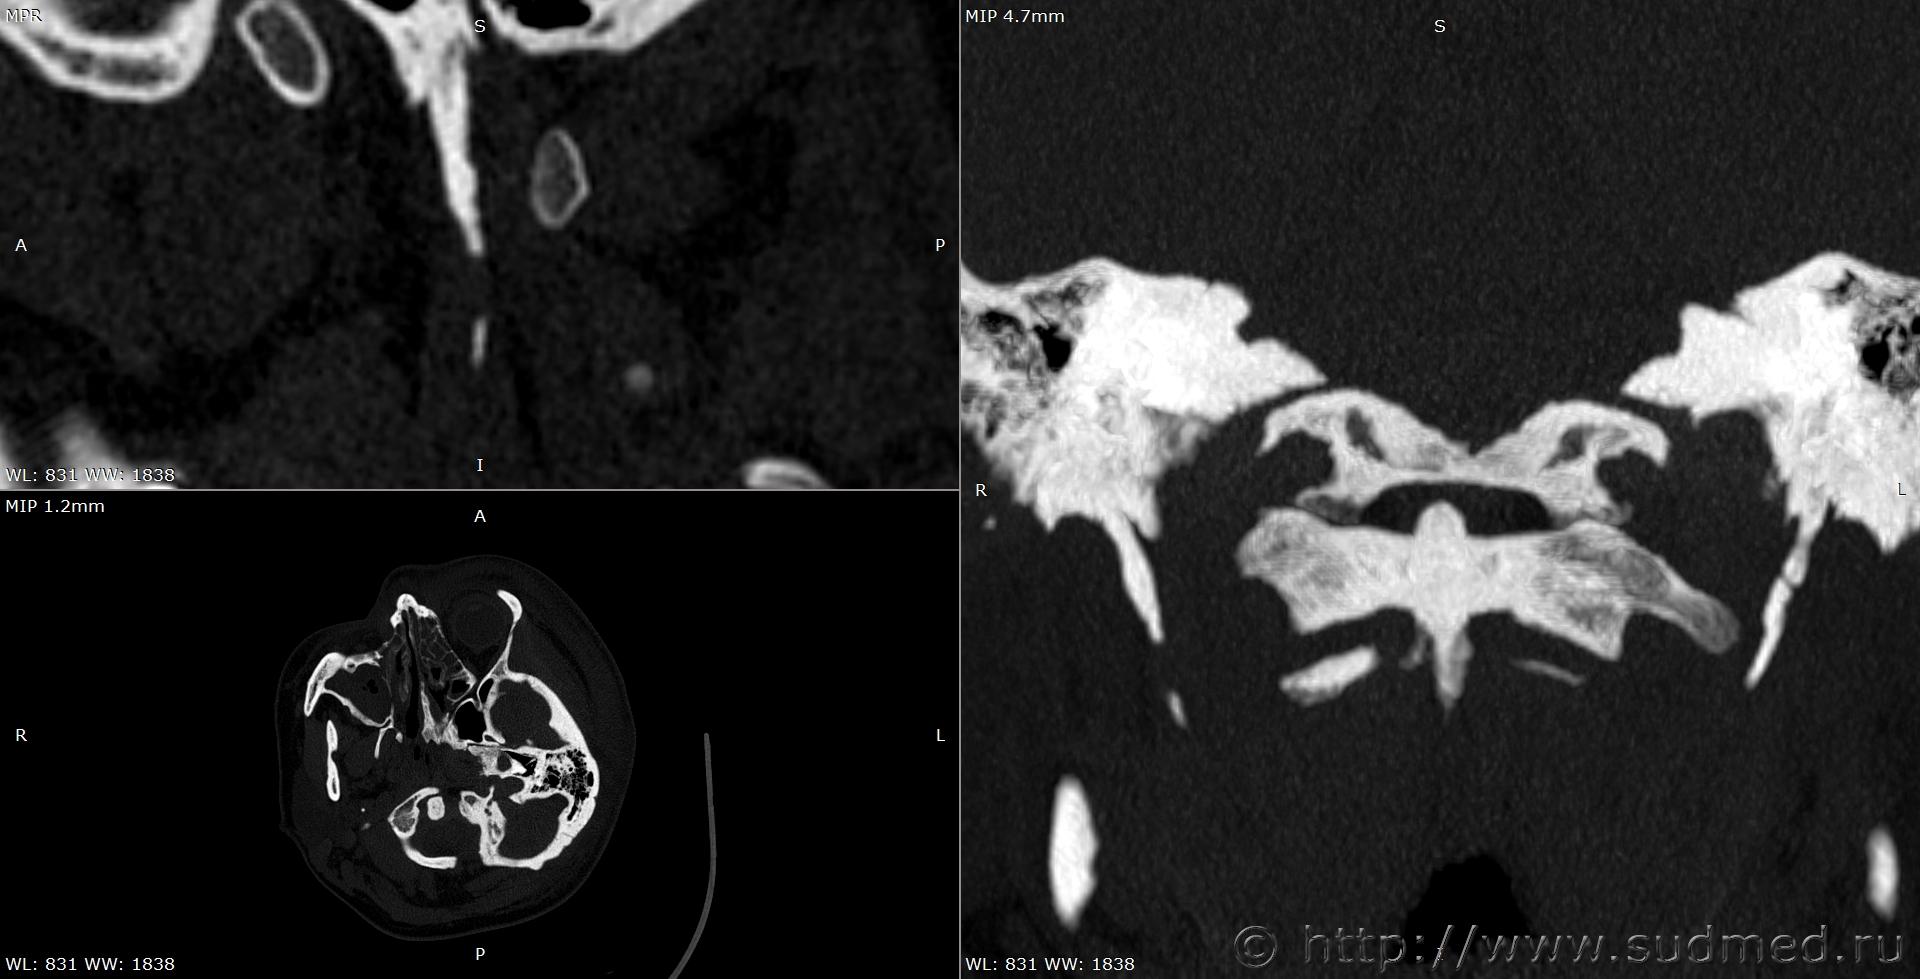

При экспертизе живого лица по медицинским документам встретились переломы шиловидных отростков височных костей. Женщина 39 лет, обратилась за медицинской помощью на 5-е сутки после травмы, тогда же провели РКТ. До этого никуда не обращалась. В протоколе РКТ отметили перелом шиловидного отростка левой височной кости, на снимках перелом на границе верхней и средней трети, дистальный отломок слегка смещен кпереди, каких-либо признаков заживления нет. Длина отростка 2,19 см. Судебная медицина - Прикрепленное изображение Также на КТ визуализируется перелом шиловидного отростка правой височной кости в нижней трети с выраженным смещением, думаю, отрывного характера (его длина 2,01 см), также без каких-либо признаков заживления Судебная медицина - Прикрепленное изображение; и гематома теменной области слева с переходом, в частности, на левую височную область, область левого сосцевидного отростка, левые околоушно-жевательную и скуловую области, левую боковую поверхность шеи Судебная медицина - Прикрепленное изображение, увеличение в объеме, нечеткость контура и разволокнение левой грудино-ключично-сосцевидной мышцы и левой ременной мышцы головы в верхней трети Судебная медицина - Прикрепленное изображение, вокруг них, в том числе кнутри от ременной мышцы, повышение плотности ПЖК Судебная медицина - Прикрепленное изображение; такие же изменения плюс повышение плотности левой подкожной мышцы шеи Судебная медицина - Прикрепленное изображение, увеличение в объеме и нечеткость контура левой околоушной слюнной железы, левая жевательная мышца не изменена Судебная медицина - Прикрепленное изображение. У подъязычной кости вижу нарушения целостности левого большого рога, но окостенение не завершено, края четко не визуализируются, поэтому о характере нарушений целостности не могу судить. Судебная медицина - Прикрепленное изображение Судебная медицина - Прикрепленное изображение В осмотрах врачей какие-либо изменения в области шеи, изменения голоса, соответствующие жалобы не отмечены; на 6-е сутки выставили острый фарингит. Помимо этой травмы есть переломы костей носа, там ничего особенного.

По срезам: шиловидные отростки какие-то тупоконечные. Подозрительна оссификация шило-подъязчных связок, что облегчает травирующему предмету возможность образовать перелом при воздействии на боковую область шеи.

Пересмотрела снимки, признаков оссификации связок нет.

Пересмотрела снимки после очередного раунда чтения литературы. Справа действительно больше похоже на оссификацию связки. Слева, скорее всего, тоже есть, перелом выше подозрительной области. Судебная медицина - Прикрепленное изображение Перелом справа снимаю. Большое спасибо за наводку!

Толщина срезов 1 мм, к слову.